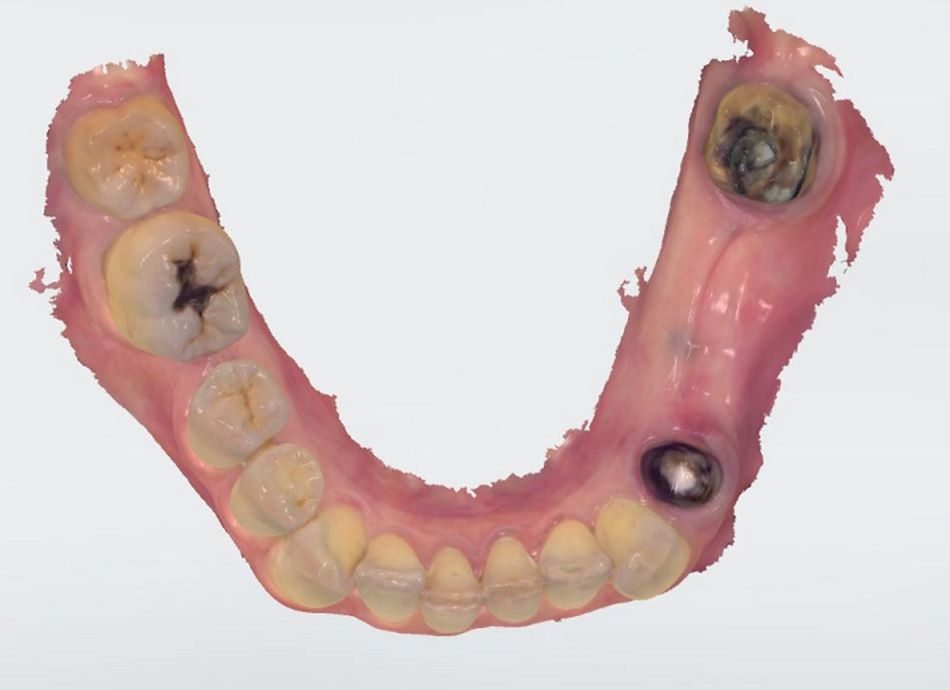

The clinical evaluation of the third quadrant showed a tooth-supported two-unit bridge (#34- #37) with apparent signs of unaesthetic coating fracture, breakage of the underlaying metal, infiltration of the underlying abutments and mobility; which  indicated the need of a new restoration, evaluation of the abutments and assessment of the edentulous area (Fig. 1).

In order to do a better assessment and evaluate the abutments, it was decided to remove the bridge prior the x-rays procedures.

The clinical evaluation of the abutments showed a limited amount of keratinized tissue in the premolar region, a regular shape of the edentulous ridge and an acceptable horizontal width. Moreover, an amalgam tattoo was also appreciated on the supracrestal area of position #35 (Fig.  2).